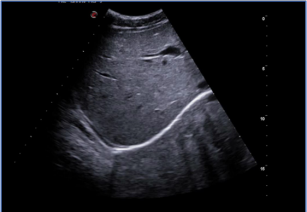

狗小肠

猫肾囊肿

大白公鼠肾脏

大白母鼠卵巢

孕鼠